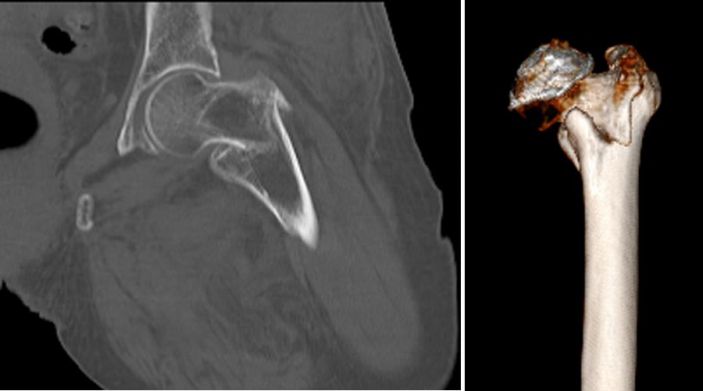

經過CT檢查發現老人家的左股骨頸骨折。此外還伴有老年性骨質疏松、高血壓病、低鈉低鉀血症等疾病。骨科吳志斌主任随即請内科、麻醉科專家會診。予監控血壓、血糖,抗骨質疏松、營養心肌等對症治療。待患者病情穩定、可耐受手術後進行手術治療。

吳志斌主任通過CT+三維重建先行拟定詳細手術方案,提前做了精心準備。根據患者的年齡特征,爲其選擇最佳的半髋置換方案,并采用雙動人工股骨頭,提高活動範圍,減少髋臼磨損。